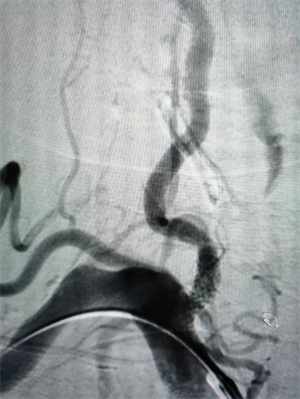

椎动脉狭窄的“通路攻坚战”

同样在元宵节当天,75岁的黄奶奶因头晕、意识丧失被送医。检查发现其左侧椎动脉闭塞、右侧椎动脉重度狭窄,广泛动脉硬化斑块形成。神经内科介入团队评估后,为其实施了脑血管造影+经皮椎动脉支架置入术。手术顺利完成,黄奶奶术后头晕症状消失。这一案例再次提醒中老年人群,尤其是有血管病危险因素的人,定期进行血管检查十分必要。

△图一:手术前右侧椎动脉重度狭窄